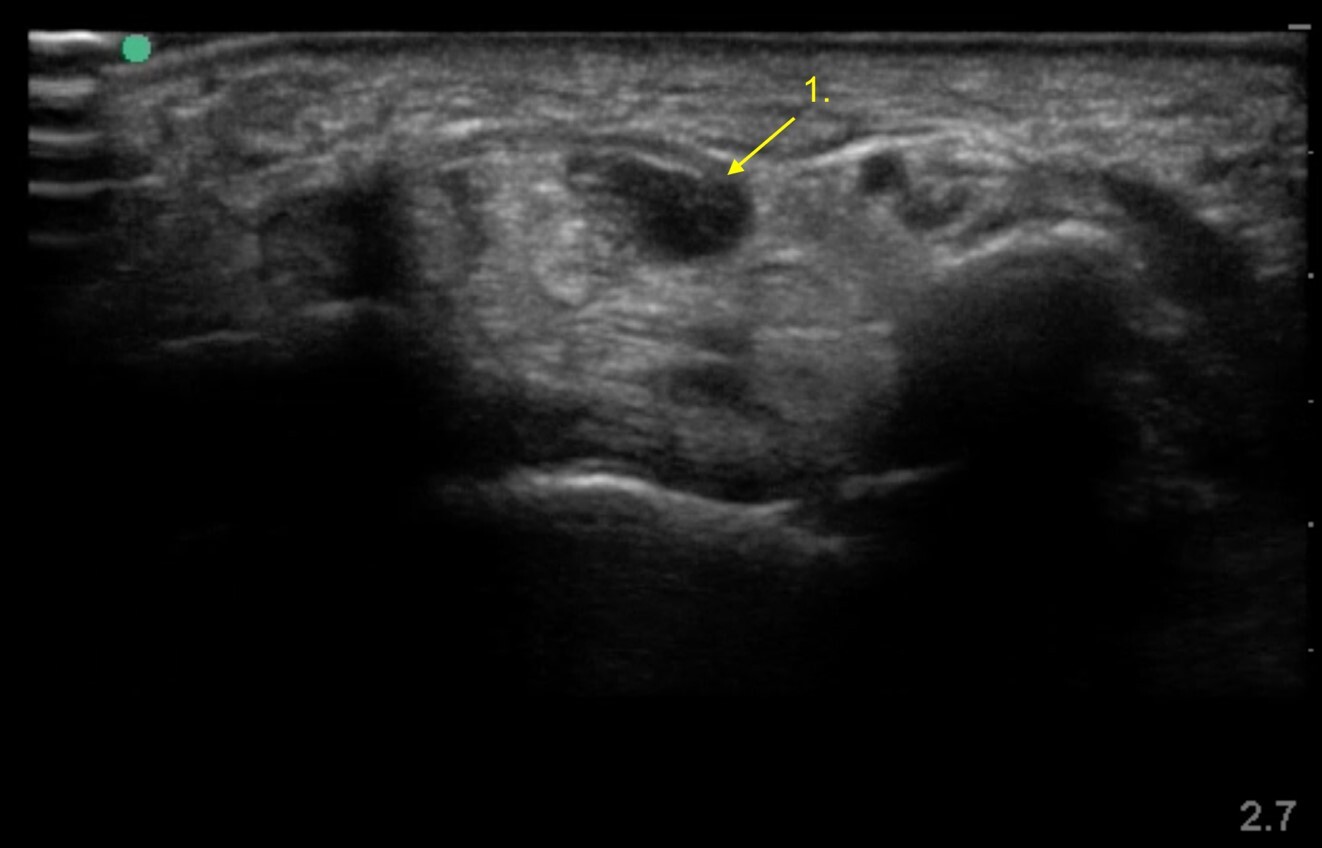

Wrist Post-Op Carpal Tunnel Release Image

Swollen Median Nerve Post-Op